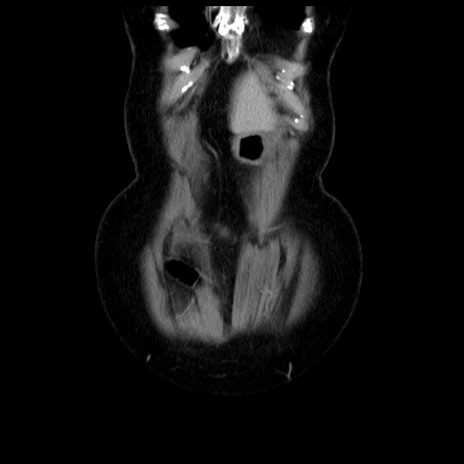

症例13(冠状断像)

横断像